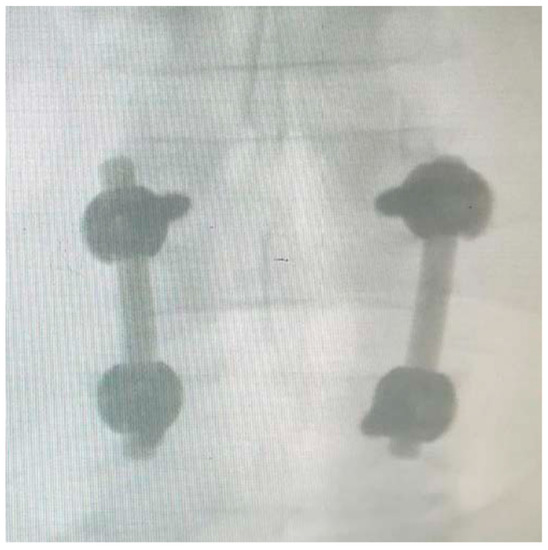

Figure 6, Figure 7, Figure 8 and Figure 9 show examples of pre- and post-operative X-ray shots.

Figure 7. Post-operative coronal X-ray check—patient code: 2ATL3L4L5110.